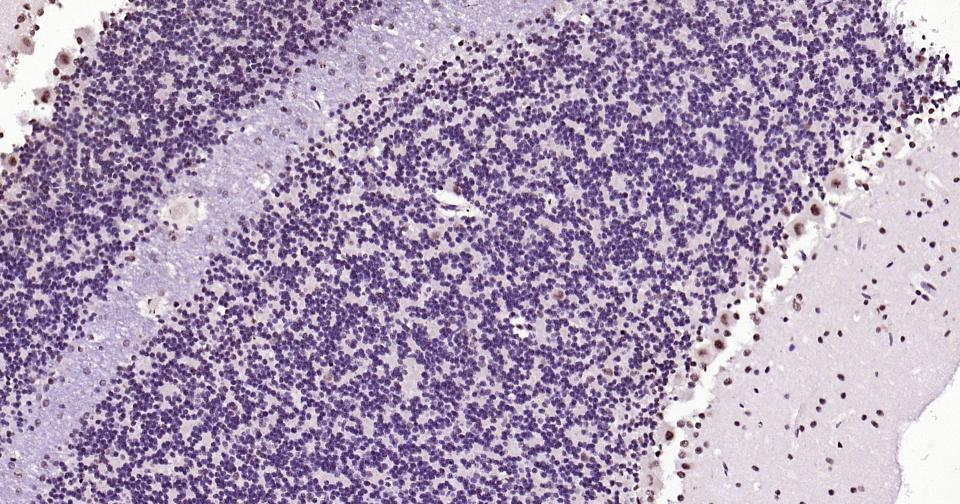

Paraformaldehyde-fixed, paraffin embedded Human Cerebellum; Antigen retrieval by boiling in sodium citrate buffer (pH6.0) for 15 min; Antibody incubation with Phospho-CREB-1 (Ser133) Monoclonal Antibody, Unconjugated(bsm-61105R) at 1:200 overnight at 4°C, followed by conjugation to the bs-0295G-HRP and DAB (C-0010) staining and DAB (C-0010) staining.